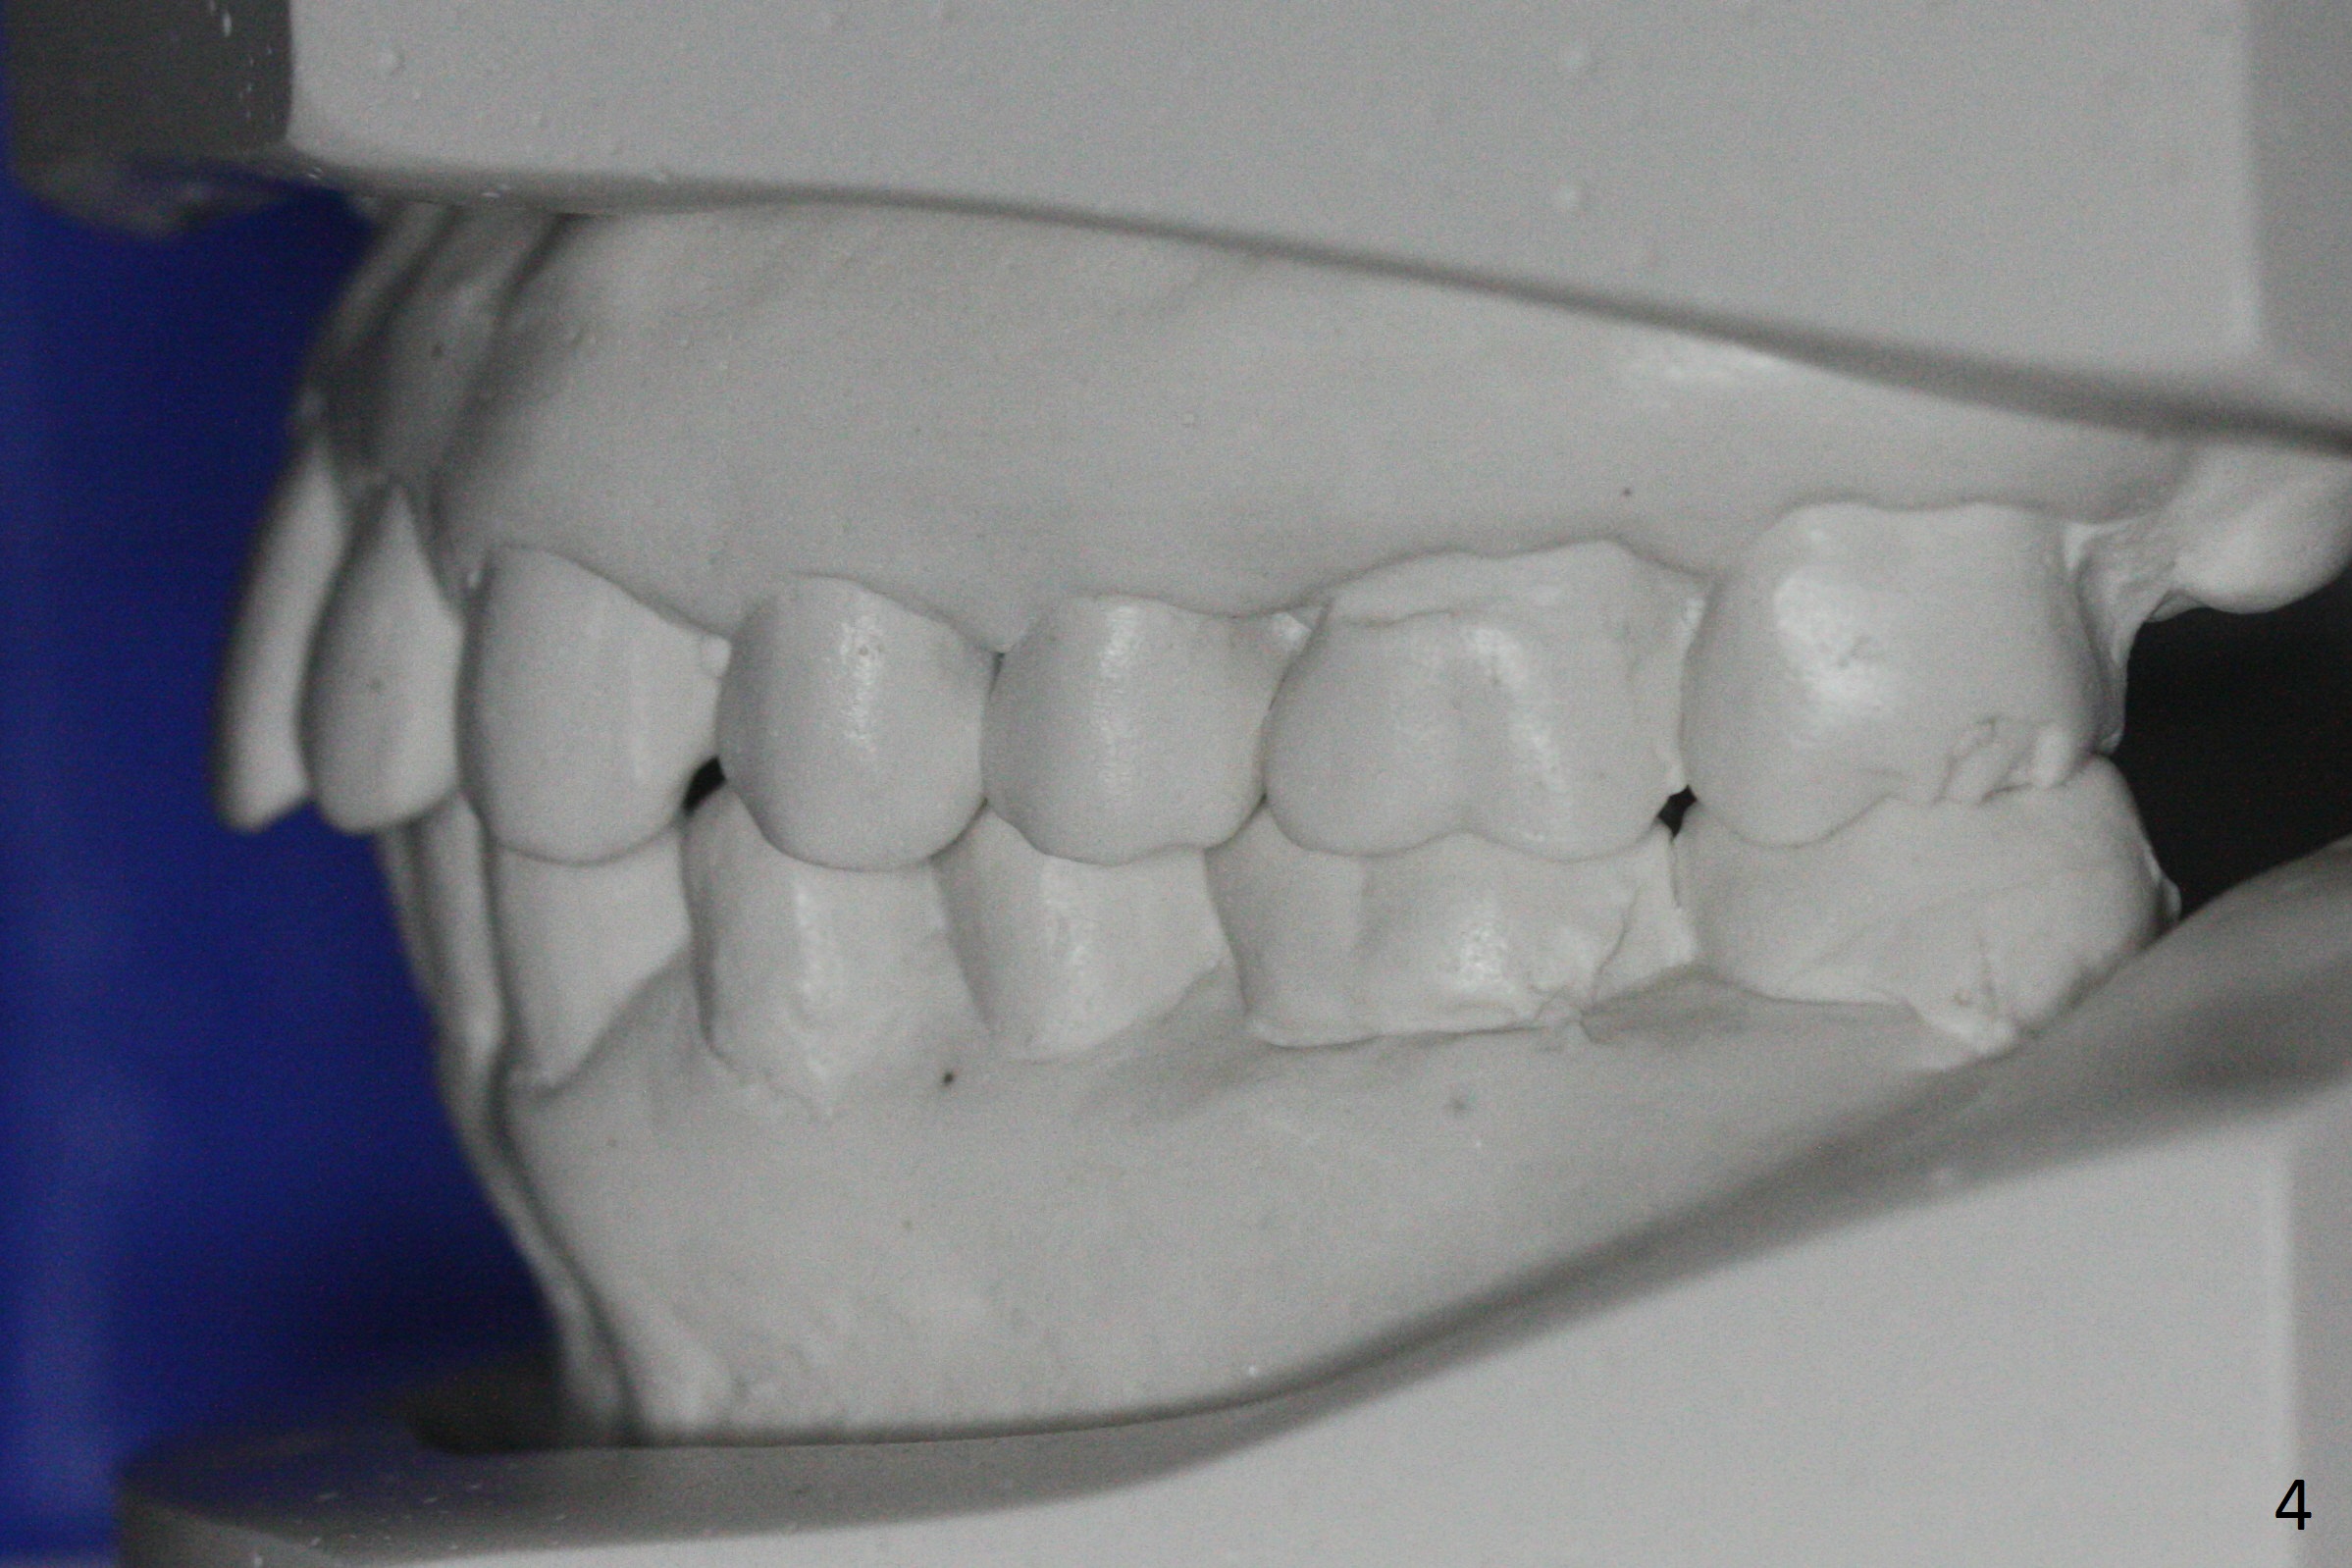

When orthodontic treatment is finished for a patient with crowding and anterior deep bite in 13 months, a diastema is found between the upper central incisors (Fig.2), which could be prevented by applying power chains for a few appointments prior to debanding. The upper anterior teeth look protrusive (Fig.4), proximal reduction seems necessary. Taking impression prior to debanding may reveal deficiency (Fig.5,6; 2nd good practice). The hidden diastemata can be revealed by use of 3-way syringe. The only prominent change is the reduction in the anterior deep bite (Fig.7,8 (posterior view)).